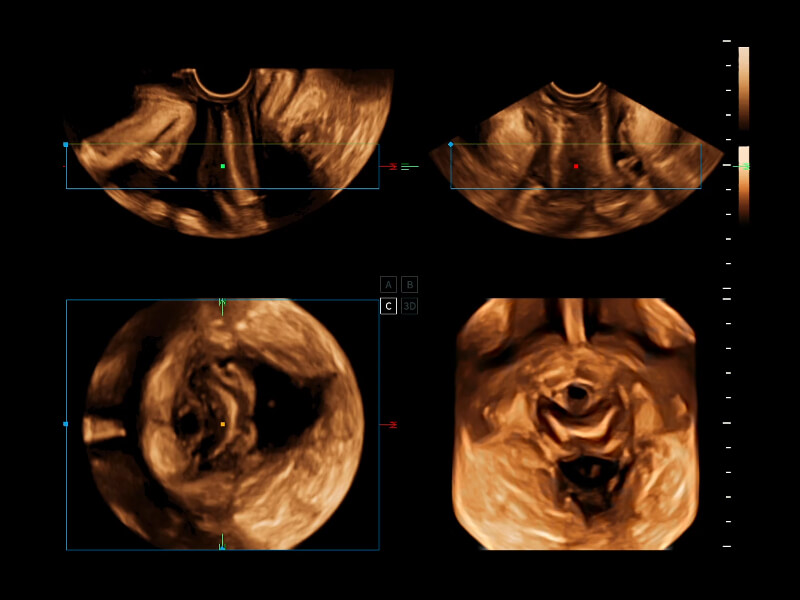

通過(guò)光照模型,使二維血流顯示出立體的效果,增加血流的敏感性、成束性,減少外溢。可以和其他不同的血流技術(shù)聯(lián)合使用,融合不同技術(shù)的優(yōu)勢(shì)。輕松應(yīng)對(duì)微小血管,增強(qiáng)血流的立體效果,提升視覺(jué)敏感性。

通過(guò)創(chuàng)新的Matrix E自適應(yīng)濾波算法,能有效濾除軟組織和噪聲信號(hào),最大限度保留超低速微細(xì)血流的信號(hào);結(jié)合超長(zhǎng)時(shí)間域算法,極大提升細(xì)微血流的敏感性和空間分辨率,更真實(shí)的反應(yīng)組織、包塊的血流灌注情況。